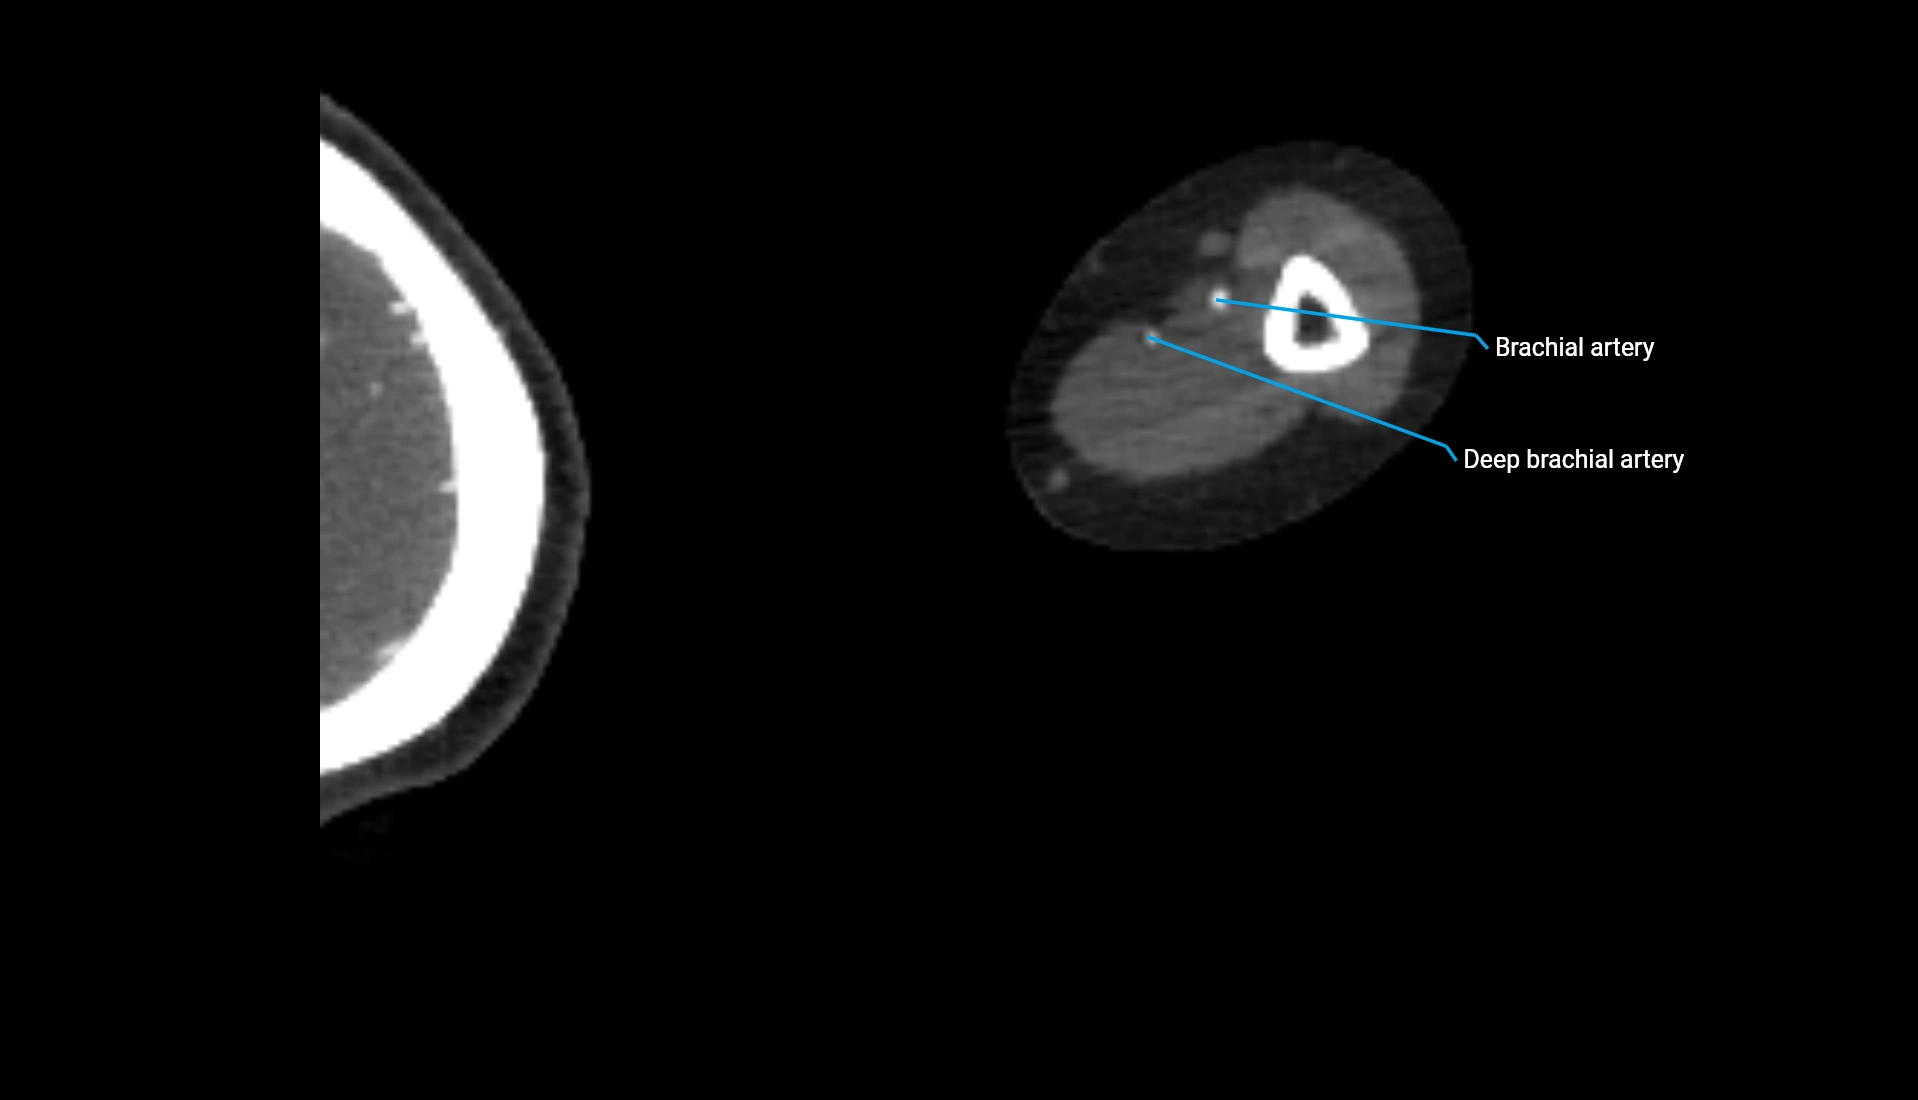

CT Appearance

Non-Contrast CT:

• Cortex: High-density, sharply defined

• Subchondral bone: Dense cancellous matrix

• Articular surface: Smooth concave contour articulating with the capitellum

• Excellent for evaluating bone integrity, alignment, and subtle fractures

Post-Contrast CT:

• Bone: No enhancement

• Joint capsule and synovium: Mild enhancement outlining the joint

• Improves contrast between soft tissues and bony margins

• Useful in detecting subtle joint abnormalities or postoperative changes